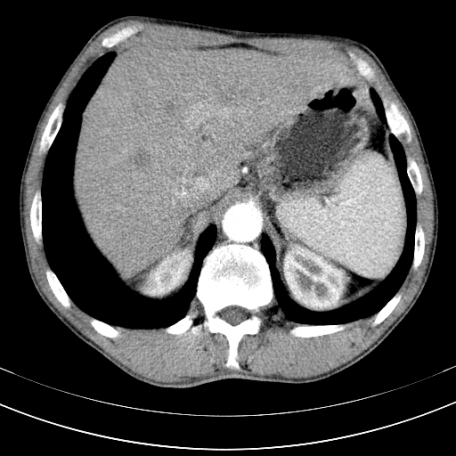

标题: CT21441:男55岁,上腹部胀痛半年余,请老师们看看是后腹膜淋巴 [打印本页]

标题: CT21441:男55岁,上腹部胀痛半年余,请老师们看看是后腹膜淋巴

腹膜后淋巴结肿大,原因待查。